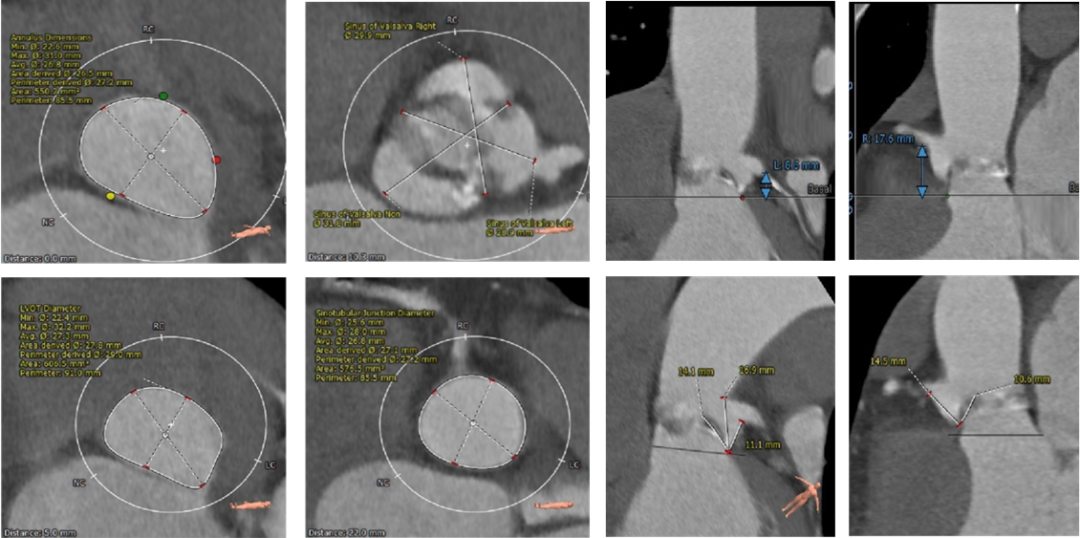

术前CT评估

CT结果显示,患者为Type1型二叶式主动脉瓣,中重度钙化合并瓣叶严重增厚。左右冠窦融合,瓣叶开口偏向一侧,钙化位置靠外侧近血管壁处,左右交界与左无交界发育不完全,形成纤维融合嵴并伴随少量钙化,瓣膜开口偏向右无对合缘侧。冠脉风险评估表明,左冠高度低,右冠高度可,左冠瓣长度大于冠脉开口与瓣叶附着缘距离,术中存在冠脉阻挡风险。综合瓦氏窦内径等因素考虑,瓣膜释放后,存在左冠状动脉阻挡风险,需术中球囊预扩时进行充分评估,必要时行冠脉保护。受钙化与瓣叶增厚影响,预估人工瓣膜形变较明显,释放过程中有潜在的下滑趋势。主动脉弓夹角锐利并弓距较短,也为这台手术增加入路和过弓难度。

主动脉根部及冠脉阻挡风险评估

瓣环上解剖结构及钙化程度分析

外周血管入路评估